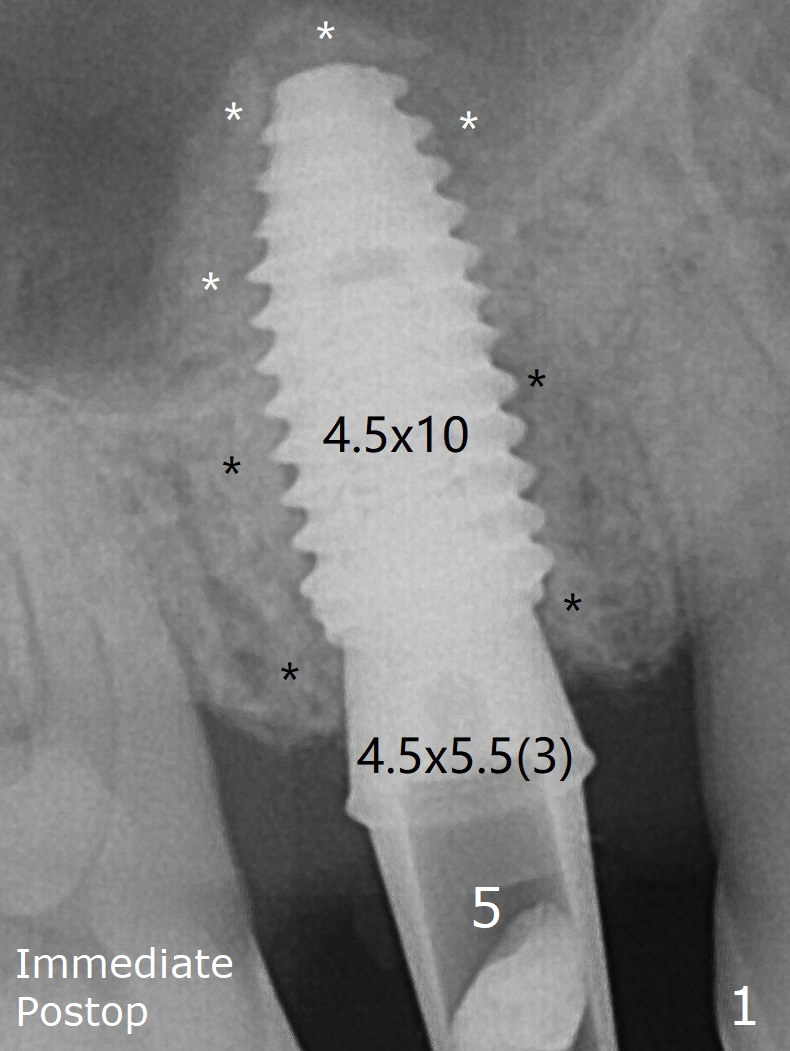

After removal and cleaning, the abutments are reseated and retorqued to 30 Ncm 11 months postop (Fig.3). The graft bone (Fig.1 black *) is indistinguishable from the native one 11 months postop.